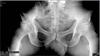

2. Do you get any groin pain? The pelvic Xray doesn't have a R/L so I'm not sure which side, but one hip joint appears to have a pincer deformity. Femoro Acetabular Impingement Syndrome. That would certainly affect your walking, and if on the side of your buttock pain, could certainly be a part of the problem.